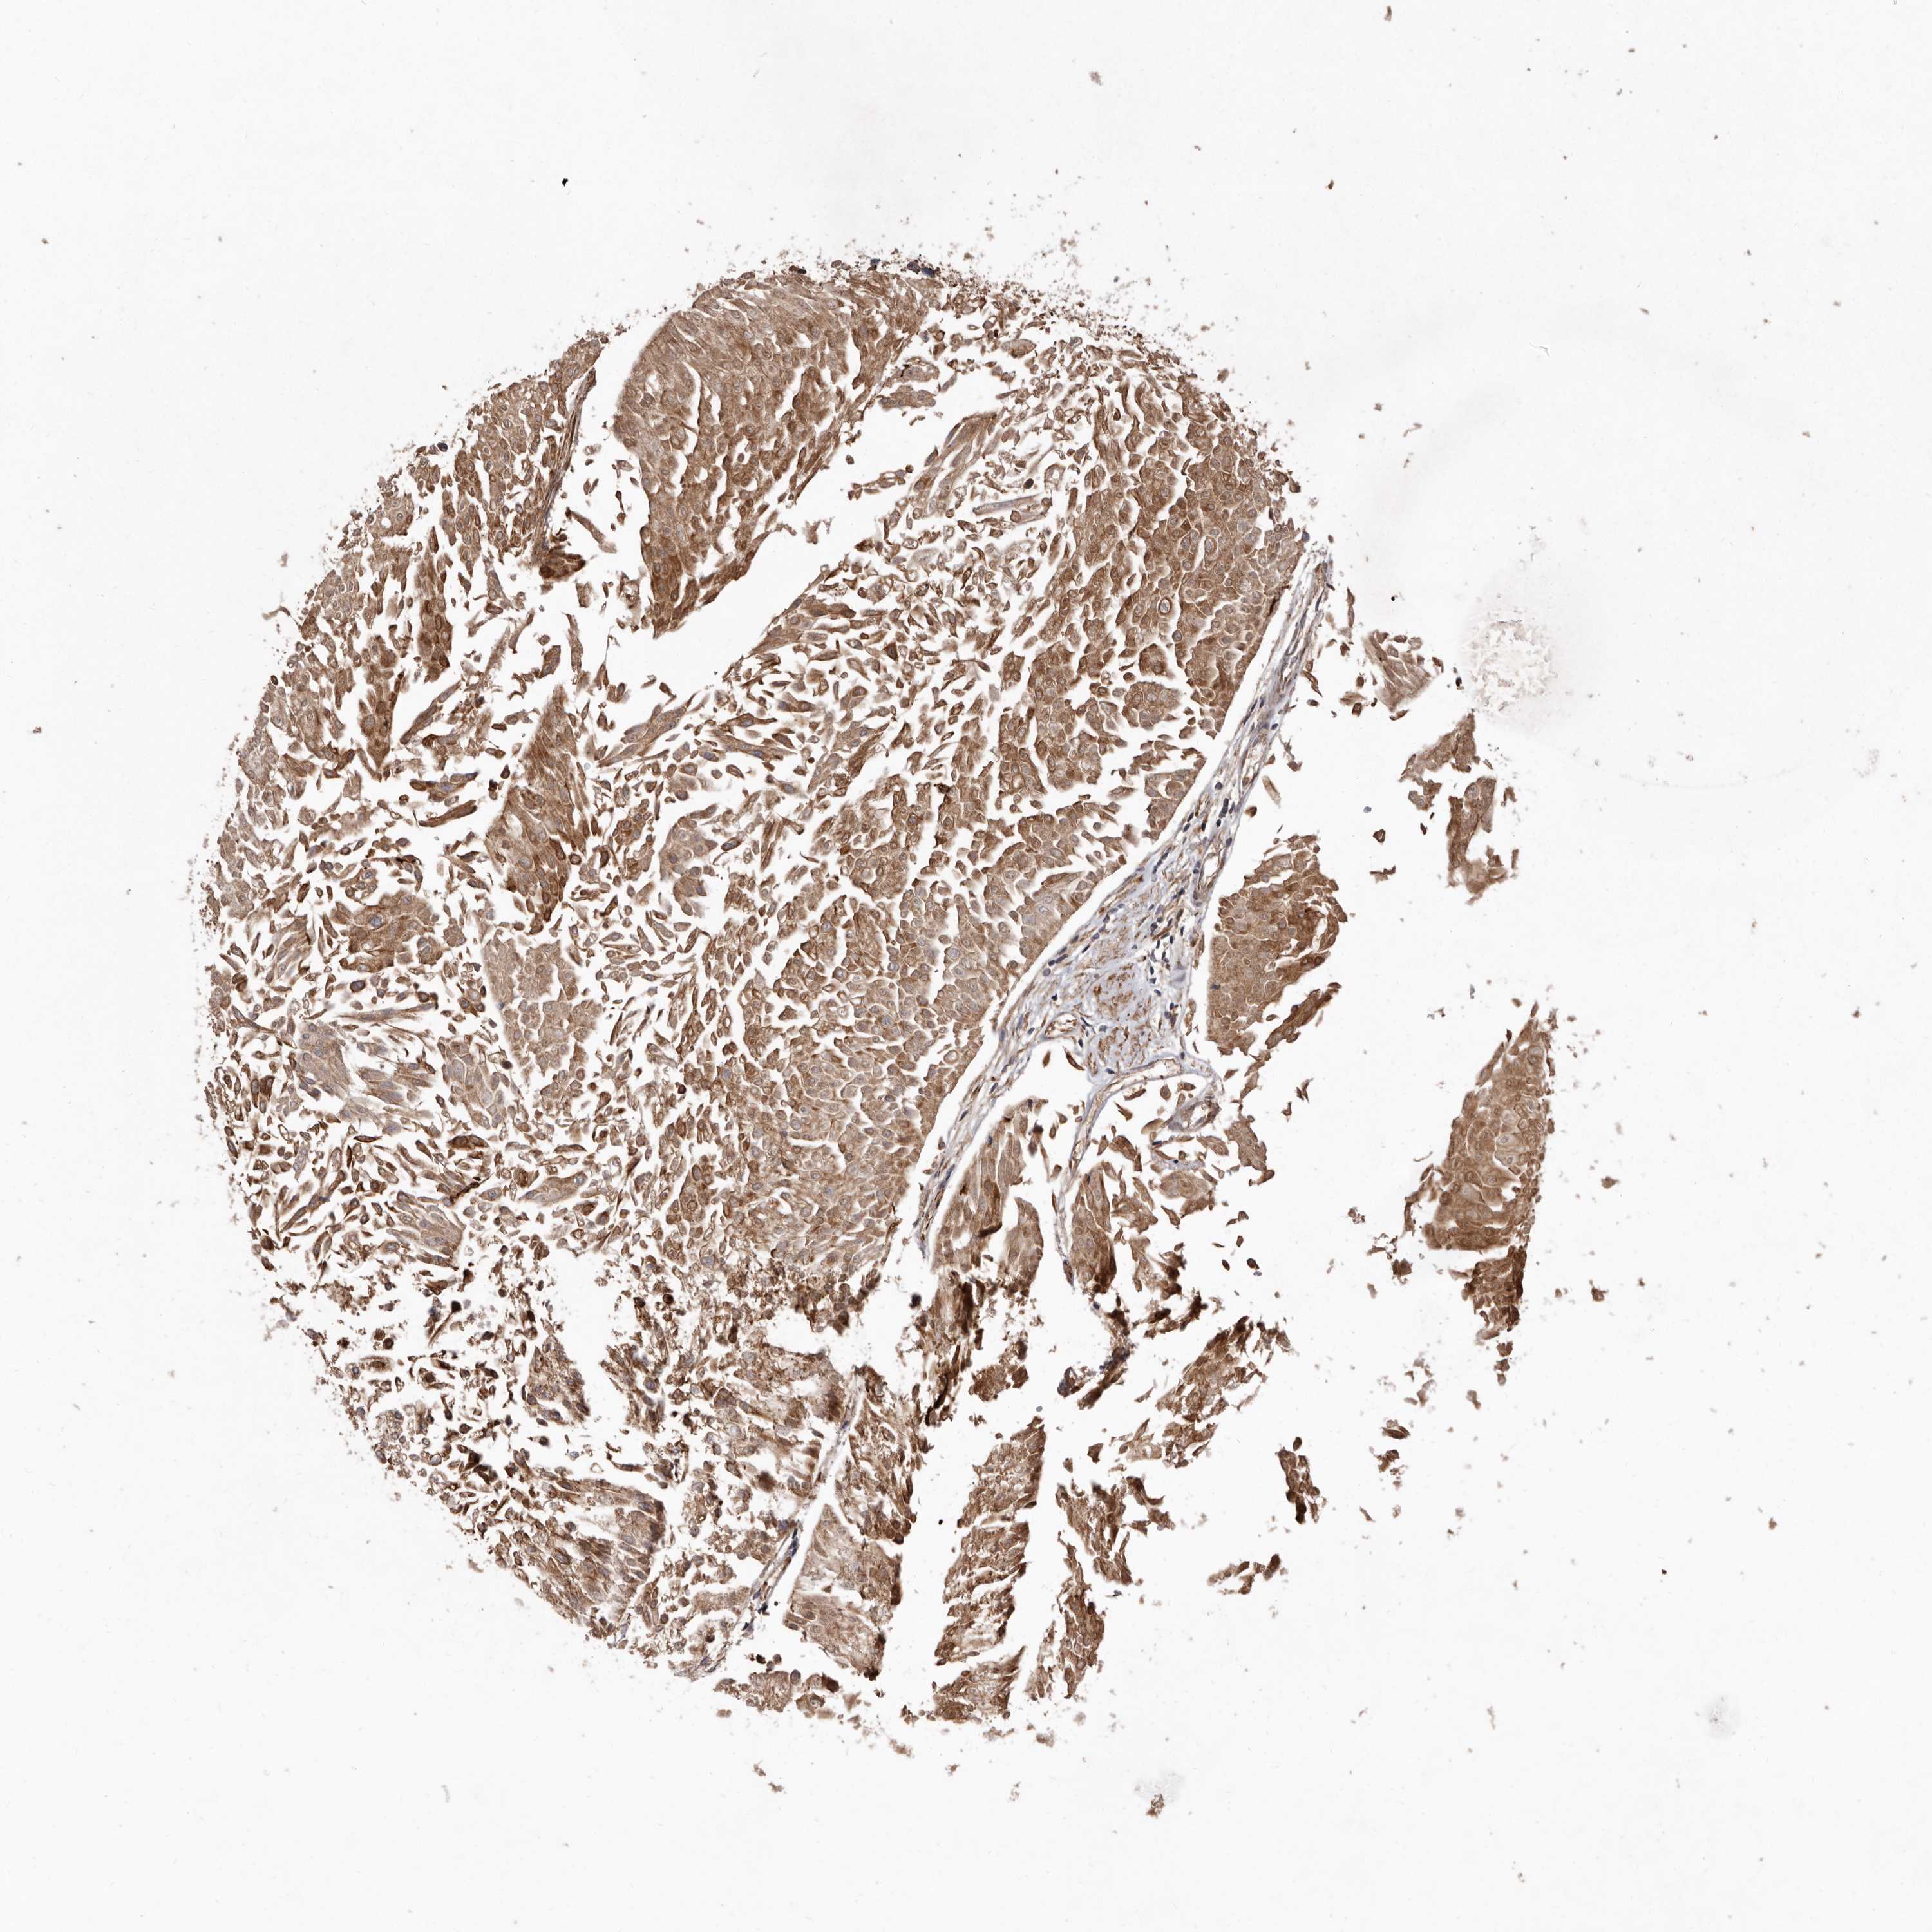

UROTHELIAL CANCER - Protein expressioni

A mouse-over function shows sample information and annotation data. Click on an image to view it in a full screen mode. Samples can be filtered based on level of antibody staining by selecting one or several of the following categories: high, medium, low and not detected. The assay and annotation is described here.

Note that samples used for immunohistochemistry by the Human Protein Atlas do not correspond to samples in the TCGA dataset.

Antibody stainingi

Antibody staining in the annotated cell types in the current human tissue is reported as not detected, low, medium, or high, based on conventional immunohistochemistry profiling in selected tissues. This score is based on the combination of the staining intensity and fraction of stained cells.

Each image is clickable and will lead to virtual microscopy that enables deeper exploration of all samples and also displays staining intensity scores, fraction scores and subcellular localization as well as patient and tissue information for each sample.

Antibody HPA028476

Antibody HPA028486

Antibody HPA028563

Urothelial carcinoma, Low grade

Urothelial carcinoma, High grade